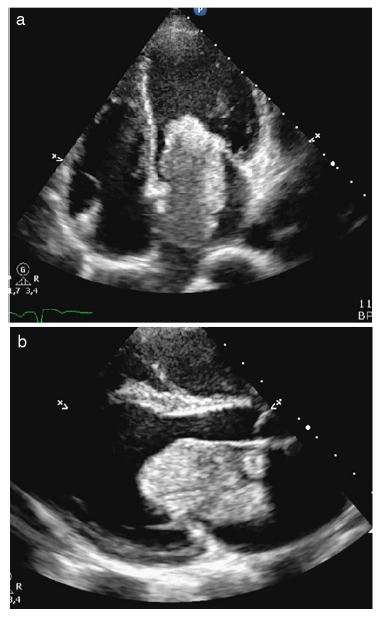

Paciente de sexo femenino, de 27 años, quien consultó a diferentes centros de salud por síntomas principales de palpitaciones y disnea de moderados esfuerzos, asociados a pérdida de peso en los últimos dos meses; ingresó remitida a la institución, donde se logró mejoría de síntomas principales con dosis de betabloqueador endovenoso. Se solicitó ecocardiograma transtorácico en cuyo reporte se describió mixoma de gran tamaño en la aurícula izquierda, mamelonado, de aproximadamente 21 cm2, con fragmentos móviles que sugerían fácil embolización, oclusión del canal de la válvula mitral en aproximadamente un 90%, adherido al septum posterosuperior con una base de implantación cercana a 1 cm de diámetro, y fracción de eyección del ventrículo izquierdo del 65% (figs. 1 a y b).

Figura 1 a y b. Ecocardiografía transtorácica, que muestra masa bien definida en la aurícula izquierda, compatible con mixoma, que ocluye el tracto de entrada del ventrículo izquierdo en un 90% (a: vista paraesternal eje largo; b: vista de cuatro cámaras).